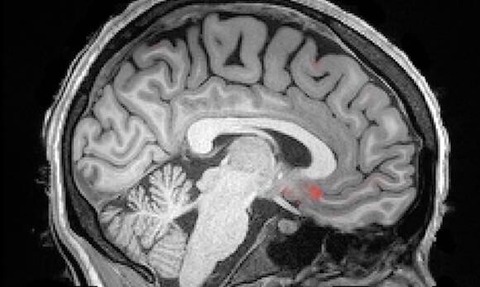

この度アメリカ・ボストン大学の研究グループは、睡眠中、脳内で脳脊髄液が毒素の清掃を行っている様子がわかるMRI映像を公開した。

マウスを対象とした動物実験によって、脳が働く過程で蓄積されてしまう毒素が睡眠で物理的に洗い流されることなら既に知られていた。『Science』(11月1日付)に掲載された今回の研究は、このことが人間にも当てはまるのかどうかを確認したものだ。

それを知るために、生物医学エンジニアのローラ・ルイス氏は、大勢の参加者にMRIの中で眠ってもらうように頼んで、そのときの脳の様子を観察するという実験を行った。

その結果、ノンレム睡眠になると、脳脊髄液の大きくゆっくりとした波が、脳全体を洗い流していることが明らかになったのである。

さらに脳波図からは、ノンレム睡眠に入ると神経細胞が同期して、スイッチのオンオフが始まることも判明した。

神経細胞が一斉に発火しなくなるので、それらはあまり酸素を必要としなくなる。このために脳への血流が減少する。

そうしてできた隙間の中に脳脊髄液が勢いよく流れ込んでくるのだ。

要するに、比喩でもなんでもなく、脳脊髄液が昼の間にたまった毒物を本当にじゃぶじゃぶと洗い流しているのである。